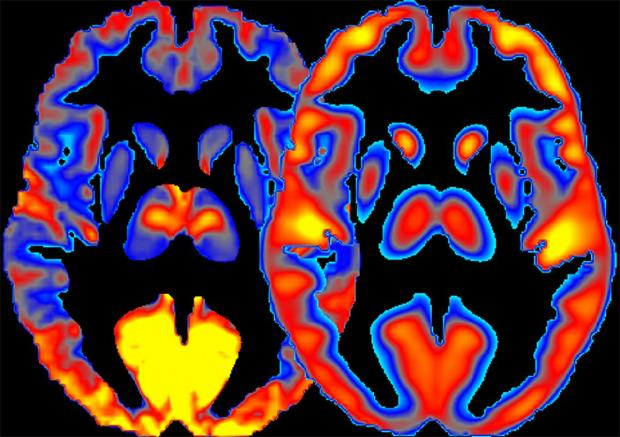

NIH scientists present a new method for combining measures of brain activity (left) and glucose consumption (right) to study regional specialization and to better understand the effects of alcohol on the human brain.

Assessing the patterns of energy use and neuronal activity simultaneously in the human brain improves our understanding of how alcohol affects the brain, according to new research by scientists at the National Institutes of Health.